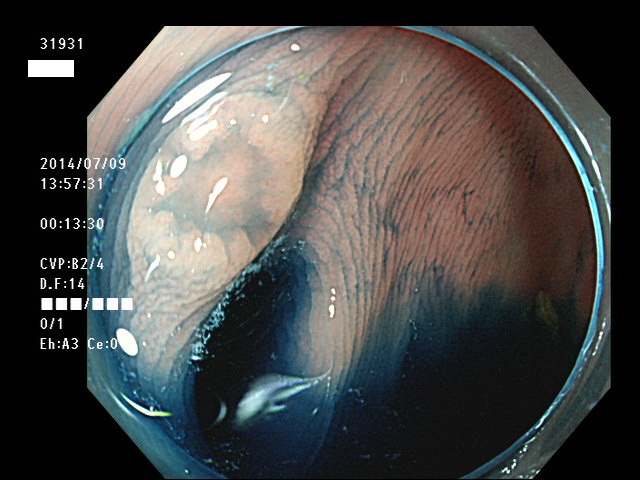

上記100名より抽出した平坦・陥凹型腺腫(=癌化の危険が高いが見落としやすい病変)の内視鏡写真